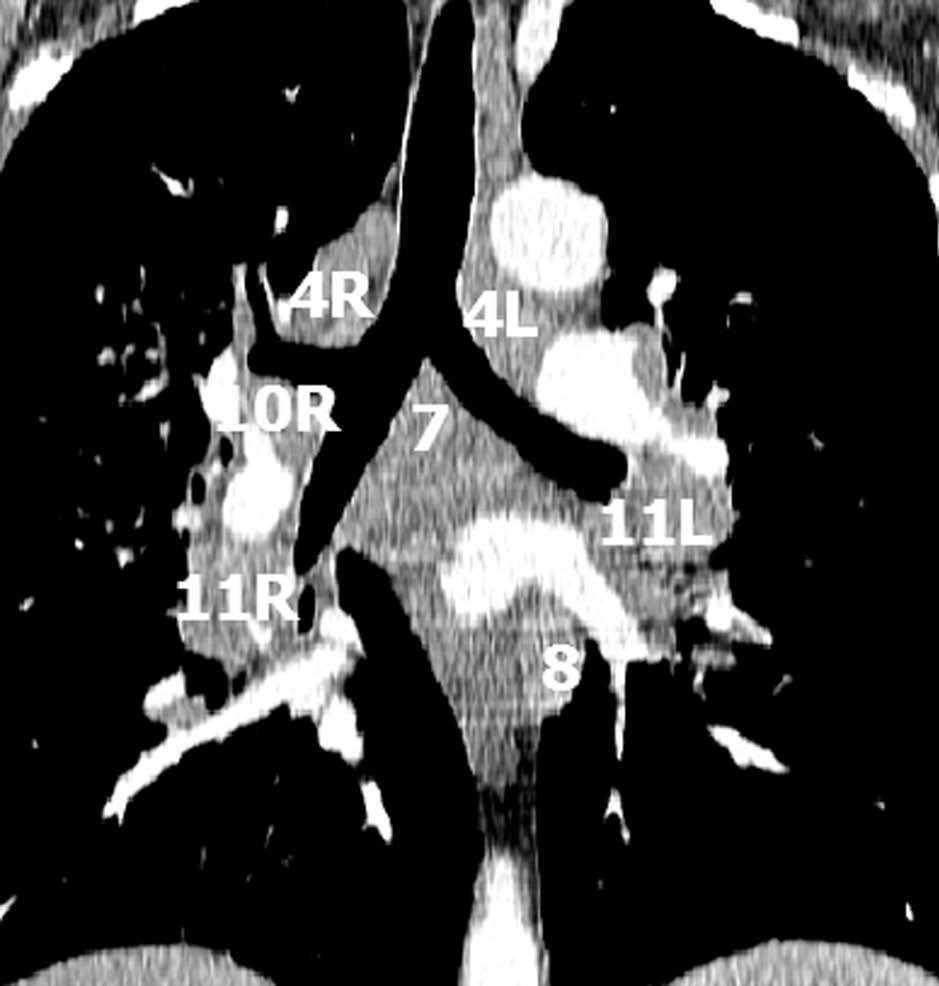

Se considera estadio N1 la afectación de ganglios homolaterales de situación intrapulmonar, peribronquial e hiliar. El estadio N2 es la afectación de los ganglios mediastínicos homolaterales, incluyendo los de la línea media, prevascular o retrotraqueal y subcarinales (niveles 3 y 7). El estadio N3 es el que incluye a los ganglios contralaterales al tumor primitivo, así como a las regiones supraclaviculares o escalenos.

La precisión de la TC para predecir la afectación ganglionar mediastínica, pese a la ayuda que suponen las reconstrucciones MPR y 3D en la valoración de determinados territorios ganglionares (espacio subcarinal, hilio o ventana aortopulmonar) (fig. 11), sigue teniendo muchas limitaciones. El único criterio que se emplea para considerar que un ganglio es patológico es el tamaño (cuando el eje corto es mayor de 10 mm, salvo en el espacio subcarinal que se acepta hasta 12 mm). El empleo únicamente de criterios de tamaño hace que la TC sea una técnica poco precisa en la valoración de la afectación ganglionar. En un metaanálisis reciente13 la sensibilidad global de la TC para estadificar el mediastino fue de un 57%, con una especificidad del 82%, un valor predictivo positivo (VPP) del 56% y un valor predictivo negativo (VPN) del 83%. Lo que es innegable es la capacidad de la TC para mostrar un mapa de los ganglios tanto hiliares como mediastínicos (fig. 12), lo cual es de gran utilidad en la determinación del factor N. La valoración del territorio hiliar puede ser compleja por la agrupación de estructuras vasculares, por lo que además de la opacificación adecuada de éstas, es de utilidad la identificación de la pérdida del ángulo de la bifurcación (carina secundaria), ya que el eje corto significativo en este territorio es de 3 mm. Como ya hemos comentado, también es de gran ayuda en esta localización el empleo de reconstrucciones (fig. 11)5.

Fig. 12.--Estaciones ganglionares para la estadificación del cáncer de pulmón. Las reconstrucciones multiplanares (MPR) son de gran ayuda para precisar los territorios ganglionares afectos. Correlación de los territorios ganglionares entre el mapa ganglionar de Mountain y Dressler y una reconstrucción coronal de un paciente con afectación adenopática mediastínica e hiliar bilateral. (A y B) Ganglios mediastínicos superiores e inferiores e hiliares. (C y D) Ganglios aórticos. AP: arteria pulmonar. Ao: aorta.